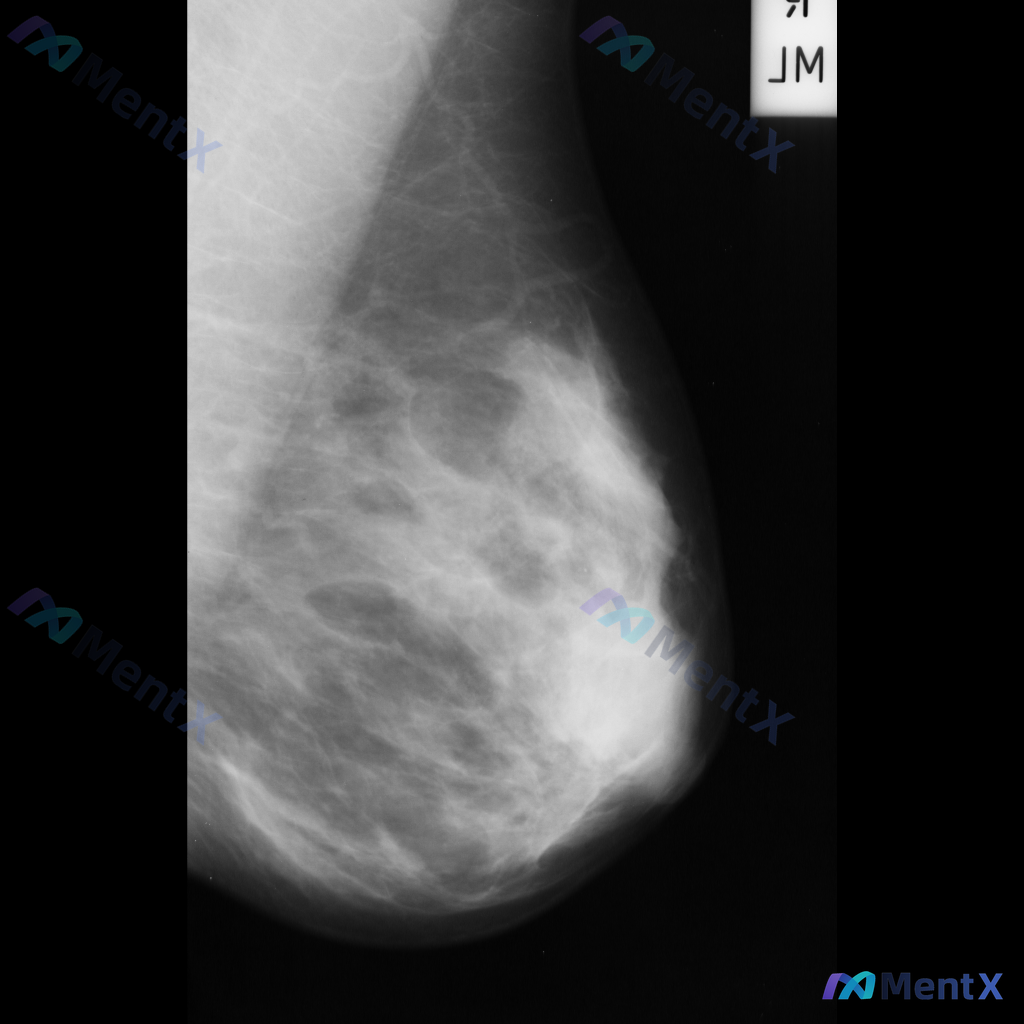

整理到一张乳腺钼靶片的读片资料,想和大家讨论下判断方向。 基本情况: - 影像:右侧乳腺内外斜位(MLO)钼靶 - 背景:致密型乳腺(多量腺体型/不均匀致密) 异常表现: 1. 右乳中上象限可见一局限性不对称致密影,形态不规则,边界部分模糊,与周围腺体融合 2. 该区域周围可见可疑结构扭曲,小梁结构...

整理到一张乳腺钼靶影像的描述资料,想请大家帮忙看看更倾向哪种情况。 【基本影像背景】 - 检查侧:右侧乳腺 - 乳腺构成:不均匀致密型(BI-RADS C型) 【影像异常发现】 - 右侧乳腺见一处不规则形高密度肿块 - 肿块边缘呈毛刺状或星芒状 - 局部伴有显著的结构扭曲 - 无明确钙化灶显示 -...

整理到一份乳腺钼靶影像的病例资料,先跟大家同步下目前的表现: - 检查部位:右侧乳腺 - 背景腺体:ACR BI-RADS C型(不均匀致密型) - 异常区域:右乳腺中上部腺体组织内 - 核心征象: 1. 可见一个不规则形的高密度肿块 2. 肿块边缘不清晰,呈毛刺状 3. 肿块周围的乳腺正常结构有牵...